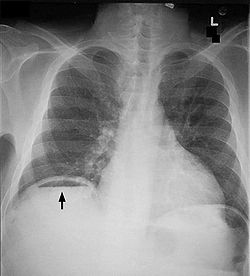

Image hydro -aerique

en niveau de estomac dans cas hernie hiatale par

roulement avec volvulus gastrique du partie hernie

du corp gastrique . Cliche pulmonaire de face |

Hernie hiatale par roulement

avecvolvulus gastrique de type mesenterico-axiale du

segment hernie du corps gastrique . Image

radiologique TDM en coupe sagitale . |